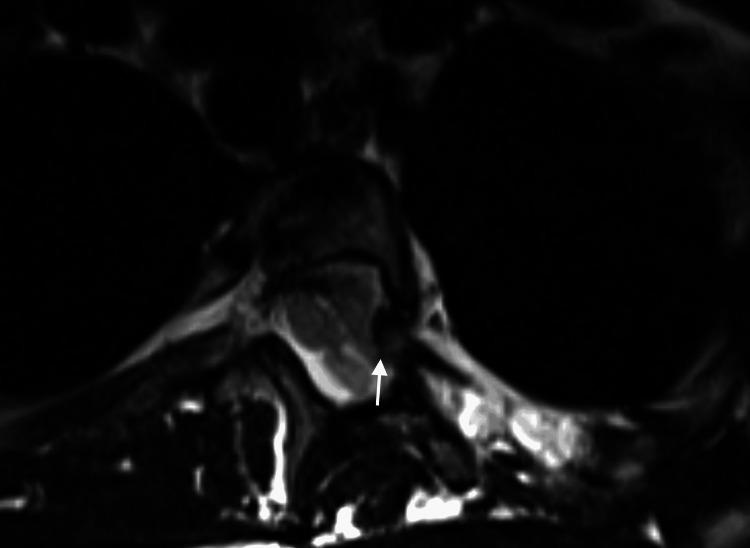

Neurofibromatosis type 1 (NF1) is frequently associated with a multitude of skeletal abnormalities including dystrophic scoliosis. A rare but severe complication of dystrophic scoliosis in NF1 is the herniation of rib heads into the spinal canal, potentially leading to devastating spinal cord compression. We present two pediatric cases of NF1-associated dystrophic scoliosis with intra-spinal herniation of rib heads. Case 1 involves a teenage male with progressive thoracolumbar scoliosis and protrusion of T10 and T11 rib heads into the spinal canal, who underwent successful posterior spinal fusion (T3-L3) with instrumentation, osteotomies, and rib head resection. Case 2 involves a teenage female with progressive thoracolumbar scoliosis and intra-spinal protrusion of T4 and T5 rib heads, who remains neurologically intact despite worsening curvature. Intra-spinal herniation of rib heads is a clinically important complication of NF1-associated dystrophic scoliosis requiring close surveillance. Familiarity with this complication is important as imaging findings may be subtle early on. Surgical management typically involves both spinal fusion and resection of rib heads to prevent neurological compromise, though timing may vary based on symptoms and progression. Multidisciplinary care is essential.

1型神经纤维瘤病(NF1)常伴有多种骨骼异常,包括营养不良性脊柱侧凸。NF1中营养不良性脊柱侧凸的一种罕见但严重的并发症是肋骨小头疝入椎管,可能导致毁灭性的脊髓压迫。我们报告两例NF1相关的营养不良性脊柱侧凸伴肋骨小头椎管内疝的儿科病例。病例1为一名青少年男性,患有进行性胸腰椎脊柱侧凸,T10和T11肋骨小头突入椎管,接受了成功的后路脊柱融合术(T3-L3),包括器械固定、截骨术和肋骨小头切除术。病例2为一名青少年女性,患有进行性胸腰椎脊柱侧凸,T4和T5肋骨小头椎管内突出,尽管脊柱侧凸加重,但神经功能仍保持完好。肋骨小头椎管内疝是NF1相关的营养不良性脊柱侧凸的一种重要临床并发症,需要密切监测。熟悉这种并发症很重要,因为早期影像学表现可能很细微。手术治疗通常包括脊柱融合和肋骨小头切除,以防止神经功能受损,不过手术时机可能因症状和病情进展而异。多学科护理至关重要。